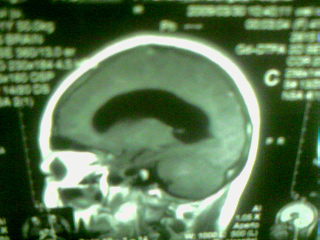

标题: MRI2125:女 45岁 头疼头晕3个月 [打印本页]

标题: MRI2125:女 45岁 头疼头晕3个月

手机照的,请各位谅解

1)考虑第四脑室脉络膜丛乳头状瘤,不排除室管膜瘤。2)阻塞性脑积水。

考虑 第四脑室室管膜瘤或脉络膜丛乳头状瘤伴梗阻性脑积水。

1)考虑第四脑室室管膜瘤,不排除脉络膜丛乳头状瘤。2)阻塞性脑积水。